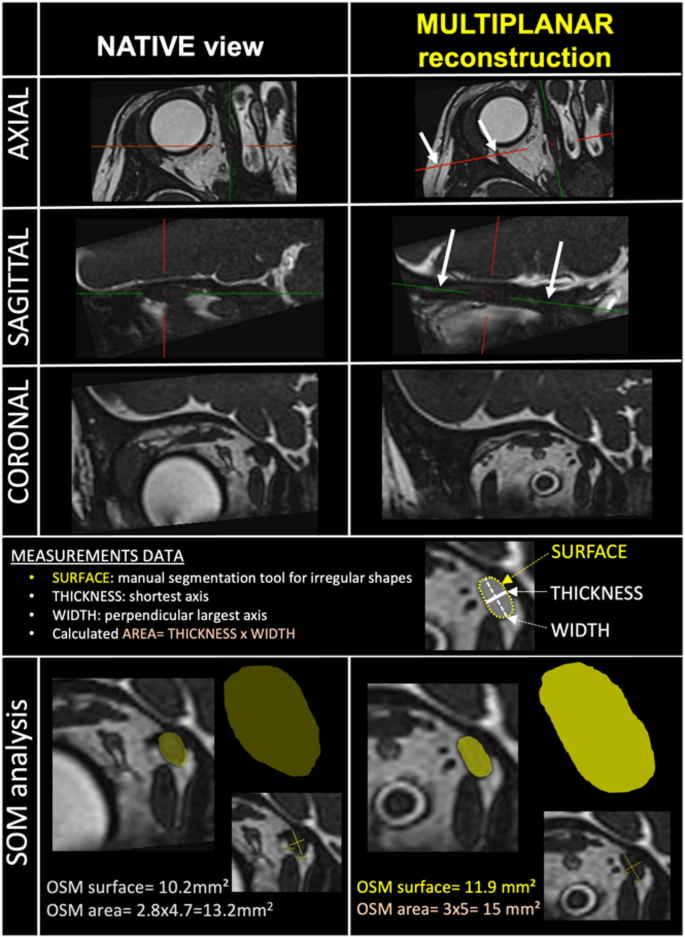

To enhance reproducibility, the multiplanar reconstruction tool was used to run through each muscle with longitudinal and perpendicular reconstructions, instead of measurements made on a classical coronal plane, which can lead to an incorrect perception of the muscle section slices (Fig. 1). Each muscle was reconstructed using a 3D tool to obtain a standardized and reproducible cross-sectional slice at its thickest region. We studied the SOM and IR muscles for each eye, blindly to palsy status but not the diagnosis. IR muscle measurements were considered as the control data, assuming that IR morphology is not affected by SOM palsy. According to the ophthalmological observation, each eye was defined as paralyzed (P) or non-paralyzed (NP). All radiological data were collected blindly to the palsy status of each patient. For both quantitative and qualitative assessments, double independent reading was performed for each patient with SOM palsy by an experienced ophthalmologist (MJL) and an experienced neuroradiologist (CC), and independent reading by an experienced radiologist was performed for control subjects (AM). All images were analyzed using the Carestream-Philips workstation. For discordant measurements in the patient group (i.e. ≥ 3 mm2 for area and ≥ 5 mm2 for surface) on inferior rectus (IR) muscle readings between both readers, a third reading was performed by a radiologist (BD), and the measurements from this third reading were used for the final analysis.

Magnetic resonance imaging-based assessment of the surface and area of the superior oblique muscle (SOM). Imaging sequence: High-resolution-3D-T2-gradient-echo CISS sequence centered on the SOM. Left column: native view, not used for study measurements. Right column: multiplanar reconstructions - perpendicular (axial view) and longitudinal (sagittal view) along the muscle axis (arrows) using an oblique three-dimensional tool, representing the measurement methodology applied in the study. The coronal muscle section slice is the plane of interest for SOM analysis. SOM analysis row: demonstrates measurement differences between native and reconstructed SOM analysis. Surface measurement: performed using the “irregular region of interest” tool. Area calculation: defined as width (larger axis of the muscle section) multiplied by length (shortest axis).

Surface and area were assessed for the quantitative analysis (Fig. 1):

Surface measurement: by manually contouring the muscle section with the “irregular region of interest” tool (in mm2).

Area calculation: width measurement defined as the larger axis of the muscle section and length measurement defined as the shortest axis; area was then calculated as follows: area = width x length (in mm²).